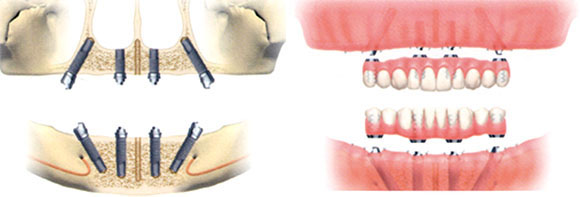

総入れ歯の方や多くの歯を失った方に、4本もしくは6本のインプラントをバランスよく埋入し、入れ歯を固定する方法です。

12本の歯を4本もしくは6本のインプラントで支え、見た目やかみ合わせで80点を取る方法です。

All-on-4 (6)では少ない本数で入れ歯を支えます。